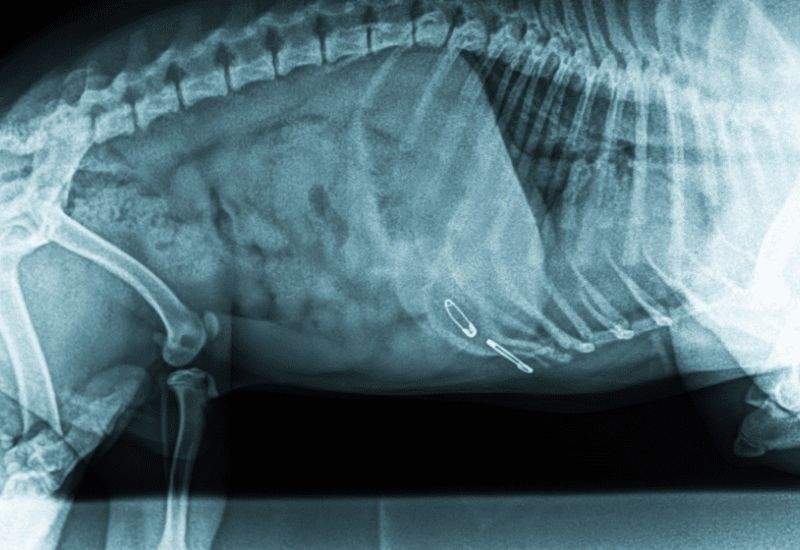

また、視力や認知機能の低下によって若い頃にはなかった異物の誤飲をしてしまい、胃腸の粘膜を傷つけて黒い便が出る事例も報告されています。

私も「シニアが梅干しの種を飲み込んでしまい真っ黒なタール便が出た」という話を耳にしました。

内視鏡での処置はシニア犬の体に負担をかける可能性があり、最悪の場合は開腹手術が必要になる重篤な事態も想定しておかなければなりません。